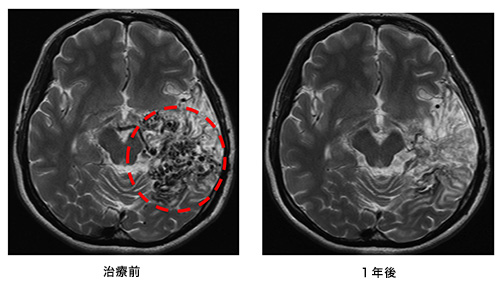

(4)放射線治療(ガンマーナイフ、サイバーナイフ)

動静脈奇形部分に集中的に放射線を照射する治療法です。小型の病変が治療対象となります。サイバーナイフ治療の前後のMRIと血管撮影の画像を下に提示します。

(画像は、日本赤十字社医療センター 脳神経外科 野村竜太郎先生のご好意による)